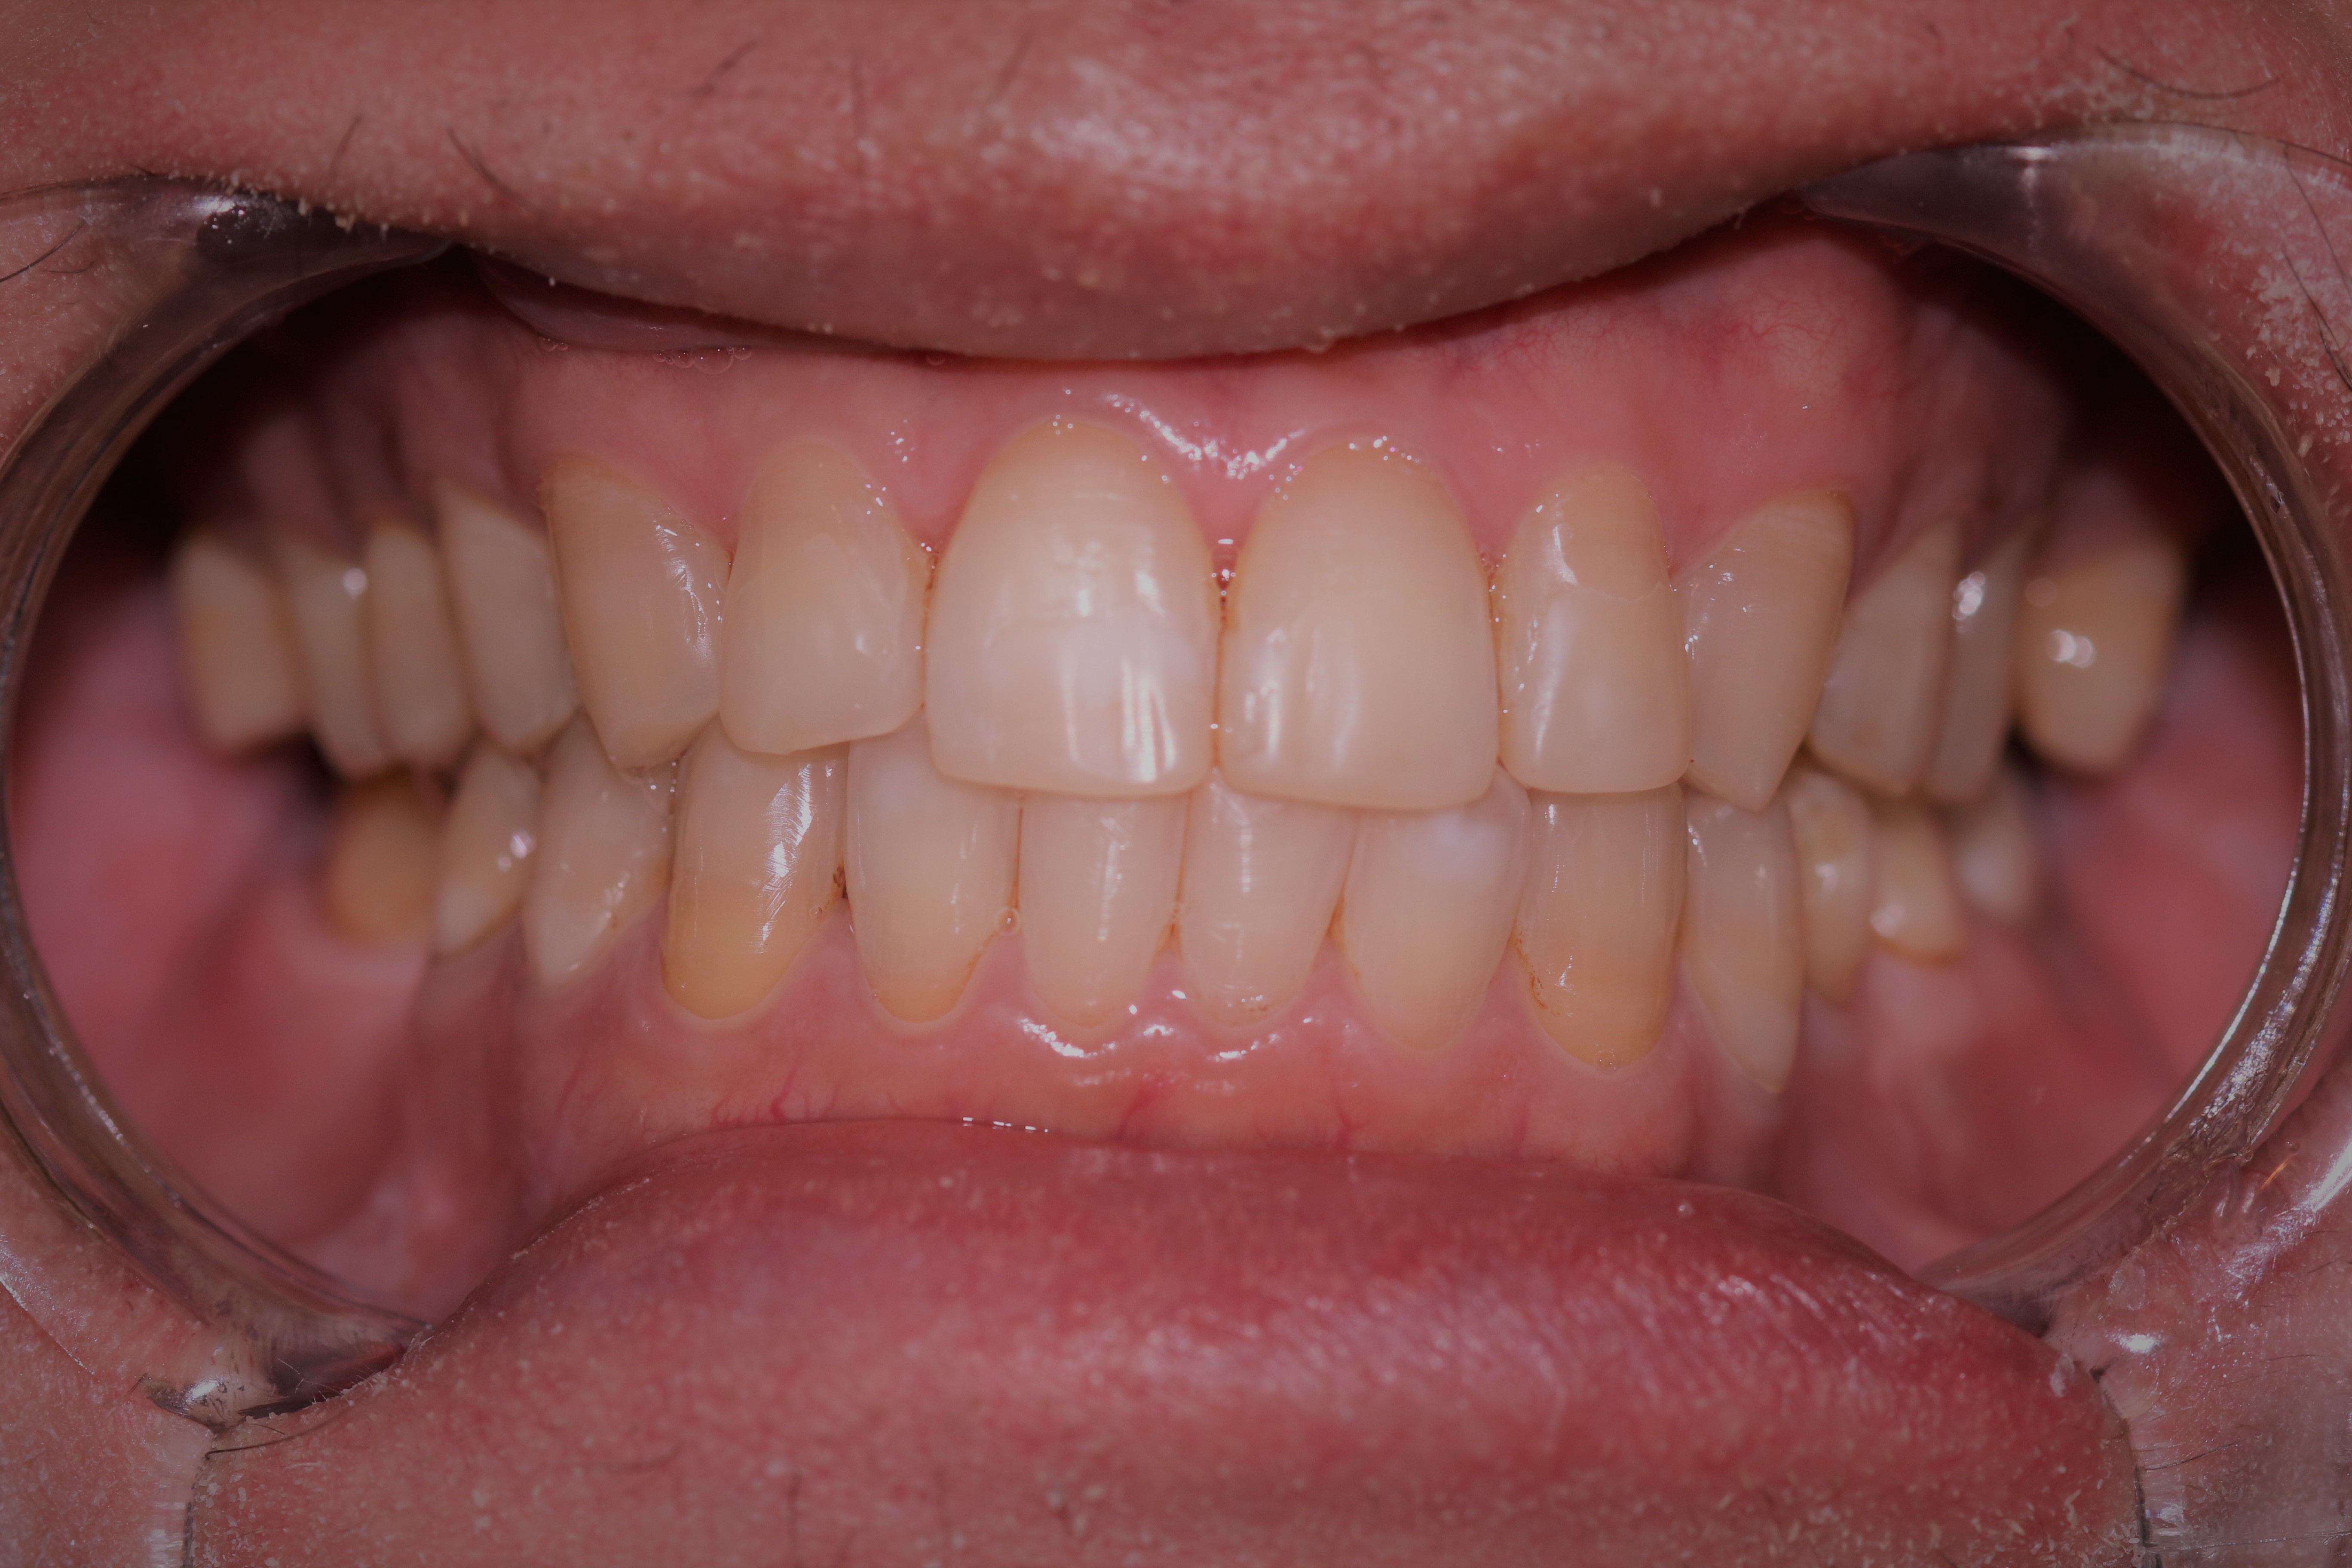

Before and After Smile

So after about 18 months worth of treatment (excluding the uneventful year 2020), the braces were removed. I thought I have a brand new smile. A few months going into the homestretch, I also noticed some changes in my appearance, not only on how my smile looked. Before the treatment, my upper jaw was concaving and my lower jaw protruding that gave my face a bulldog appearance. Because my upper jaw is concaving, a portion of my upper lip seems to be submerged or buried. After the treatment, I have noticed that my cheekbones have become more prominent (probably due to the upper portion of the skull, jaw, and teeth now resting nicely on the lower jaw and teeth) and my upper lip is fuller, aside from my teeth that are now even and bite aligned.